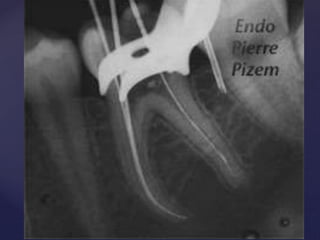

1. Apical

Apical